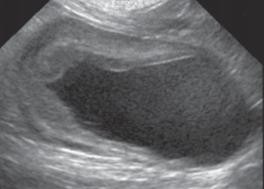

Siêu âm đóng vai trò quan trọng trong chẩn đoán bệnh viêm tử cung, các phát hiện siêu âm điển hình phù hợp với viêm tử cung bao gồm chứng to tử cung, thành tử cung dày lên, thay đổi tăng sinh nội mạc tử cung, sừng tử cung hình ống xoắn do chất lỏng gây ra, và giảm âm vang trong lòng tử cung chứa dịch. Siêu âm có thể phân biệt viêm tử cung với các mô mềm khác, khiến tử cung căng lên và là điều bắt buộc để đánh giá về sự hiện diện của tăng sản nội mạc tử cung và sự nguyên vẹn của nội mạc tử cung (Nyland & Mattoon, 2002; Wallace & Casal, 2018). Tương tự nghiên cứu Hagman (2018) khi sử dụng siêu âm để chẩn đoán bệnh viêm tử cung và tăng sản nội mạc tử cung, trên chó mắc tăng sản nội mạc tử cung quan sát thấy thành tử cung dày lên và có các cấu trúc nang không cản âm và không có dịch trong tử cung, trong khi đó với trường hợp chó vừa bị viêm tử cung và tăng sản nội mạc tử cung quan sát thấy thấy thành tử cung dày lên và có các cấu trúc nang không cản âm và quan sát dịch trong tử cung. Tương tự nghiên cứu Mattei & cs. (2018) khi thực hiện chẩn đoán trên một chó Labrador Retriever 7 tuổi chưa sinh sản được đưa đi viện vì tiền sử nôn mửa, chán ăn trong 1 ngày, đi tiểu nhiều, khát nước nhẹ và có dấu hiệu mệt mỏi, sưng âm hộ với một ít lượng dịch màu vàng. Chụp X quang bụng cho thấy một khối giãn nở chủ yếu chứa đầy khí, ban đầu nghi ngờ có tắc ruột non. Sau khi kiểm tra siêu âm phát hiện một bên sừng tử cung có vách giảm âm đồng nhất và chứa khí và chất lỏng có độ

Hình 4.26. Hình ảnh siêu âm về thai (mũi tên)